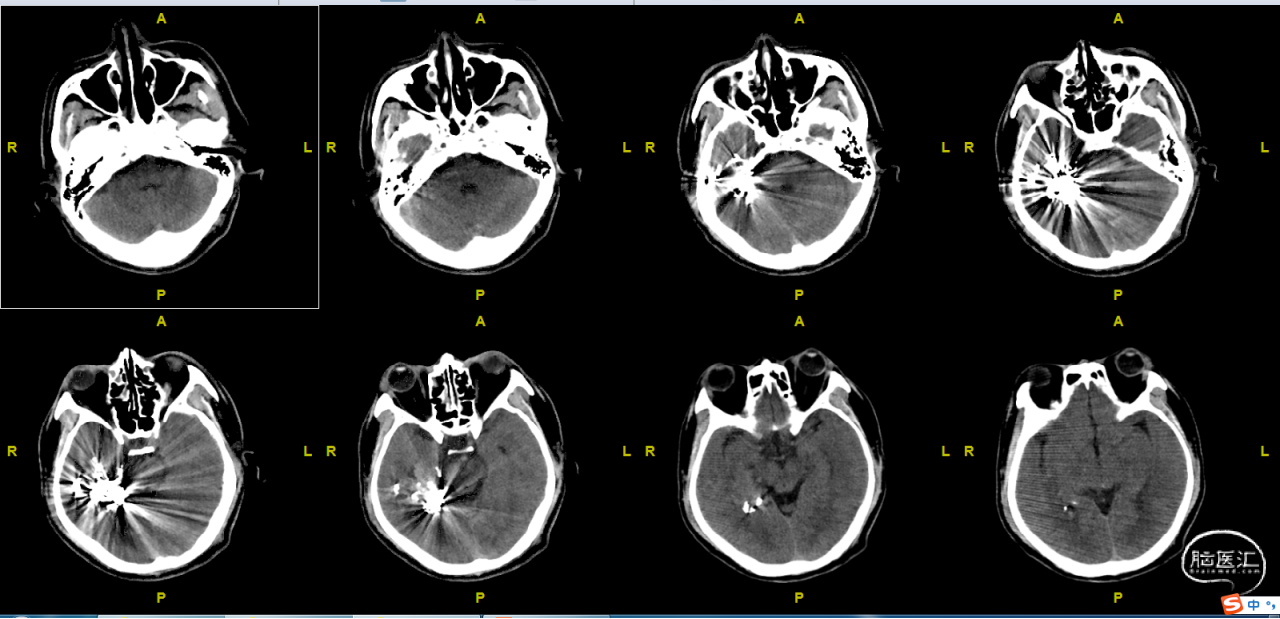

术前CT

栓塞术后CT

术后CT(术后第一天)

入院诊断:右颞底AVM

●术前诊断:右颞底面AVM